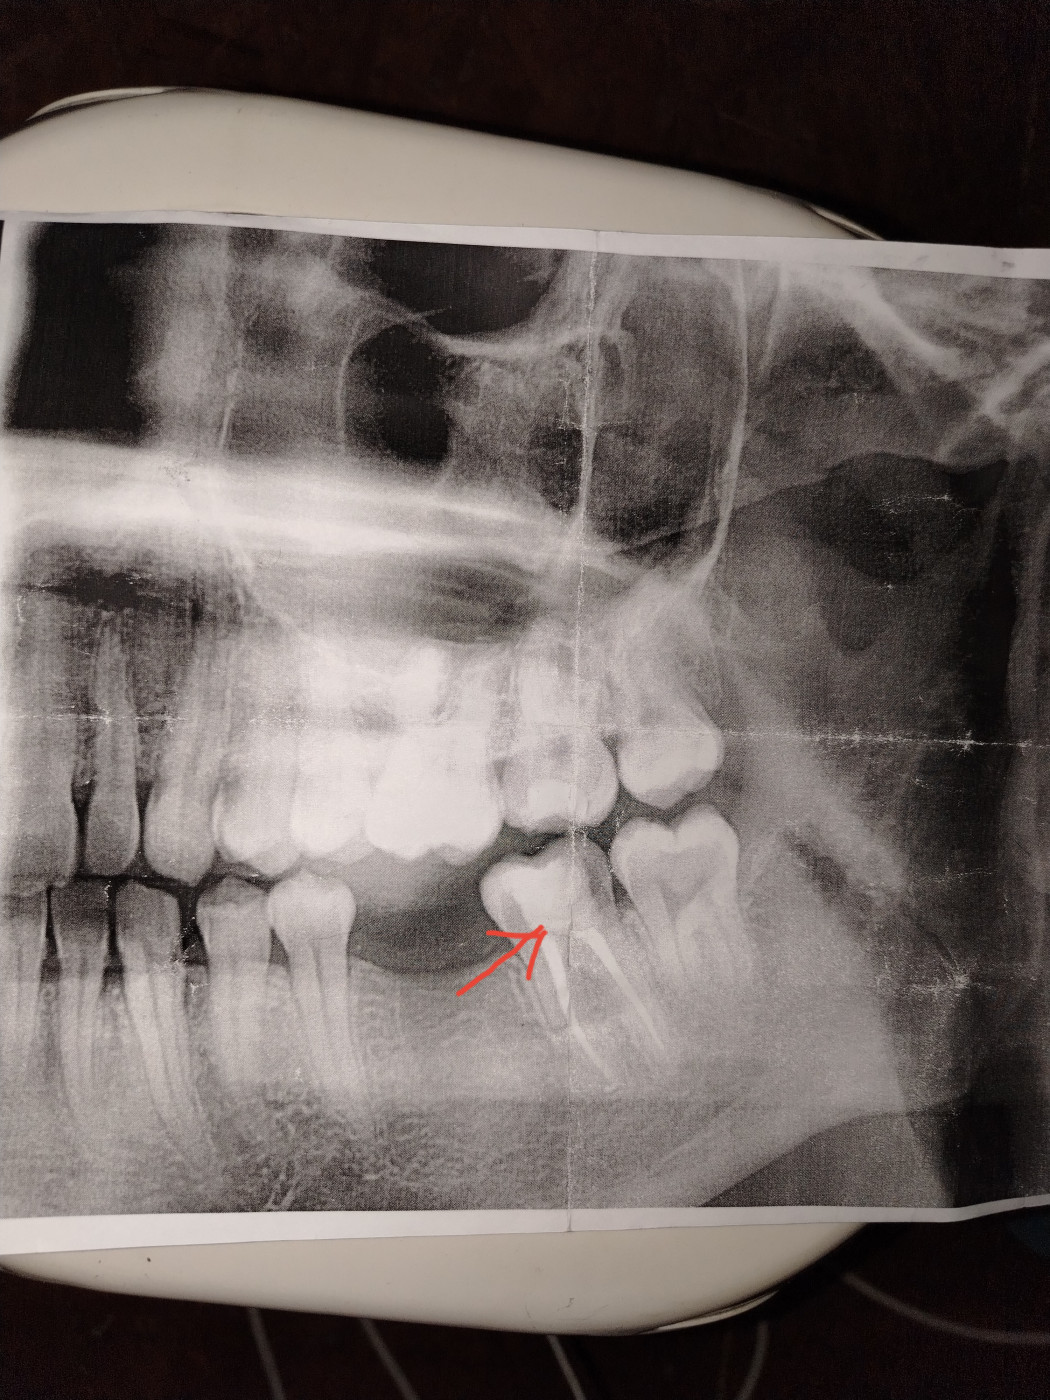

Можно ли спасти зуб?

Что может быть с зубом?